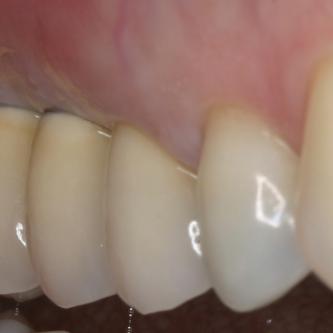

Exemple 8: Un implant au niveau de la prémolaire supérieure droite.

Exemple 8

Exemple 8: La couronne en place.